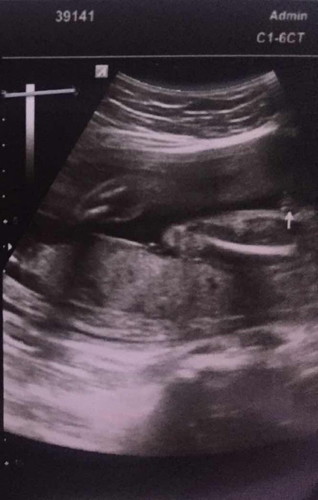

ช่วยดูเพศลูกหน่อยค่ะ

แบบนี้คัยดูออกบ้างค่ะว่าเพศชายหรือ หญิง เราดูไม่ออกเลย

หญิงจ้าบ้านนี้ทีมกุมภาก็ผู้หญิงเหมือนกันค่ะ

เห็นเป็นกลีบนะคะ น่าจะหญิงค่ะ

ชัดมาก ได้ลูกสาวค่ะคุณแม่

ลูกสาวเลยค่ะแบบนี้ ☺️

ญ ค่ะแม่

ญ ค่ะ